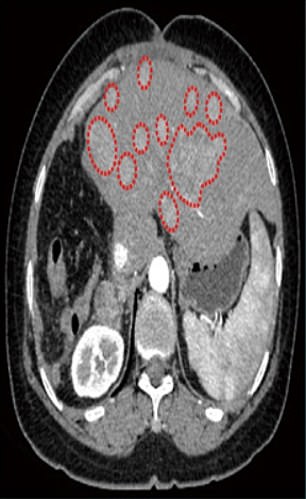

And one-and-a-half months after the patient received the experimental therapy

Liver cancer shown before treatment (left) and one-and-a-half months after the patient received the experimental therapy that uses a virus